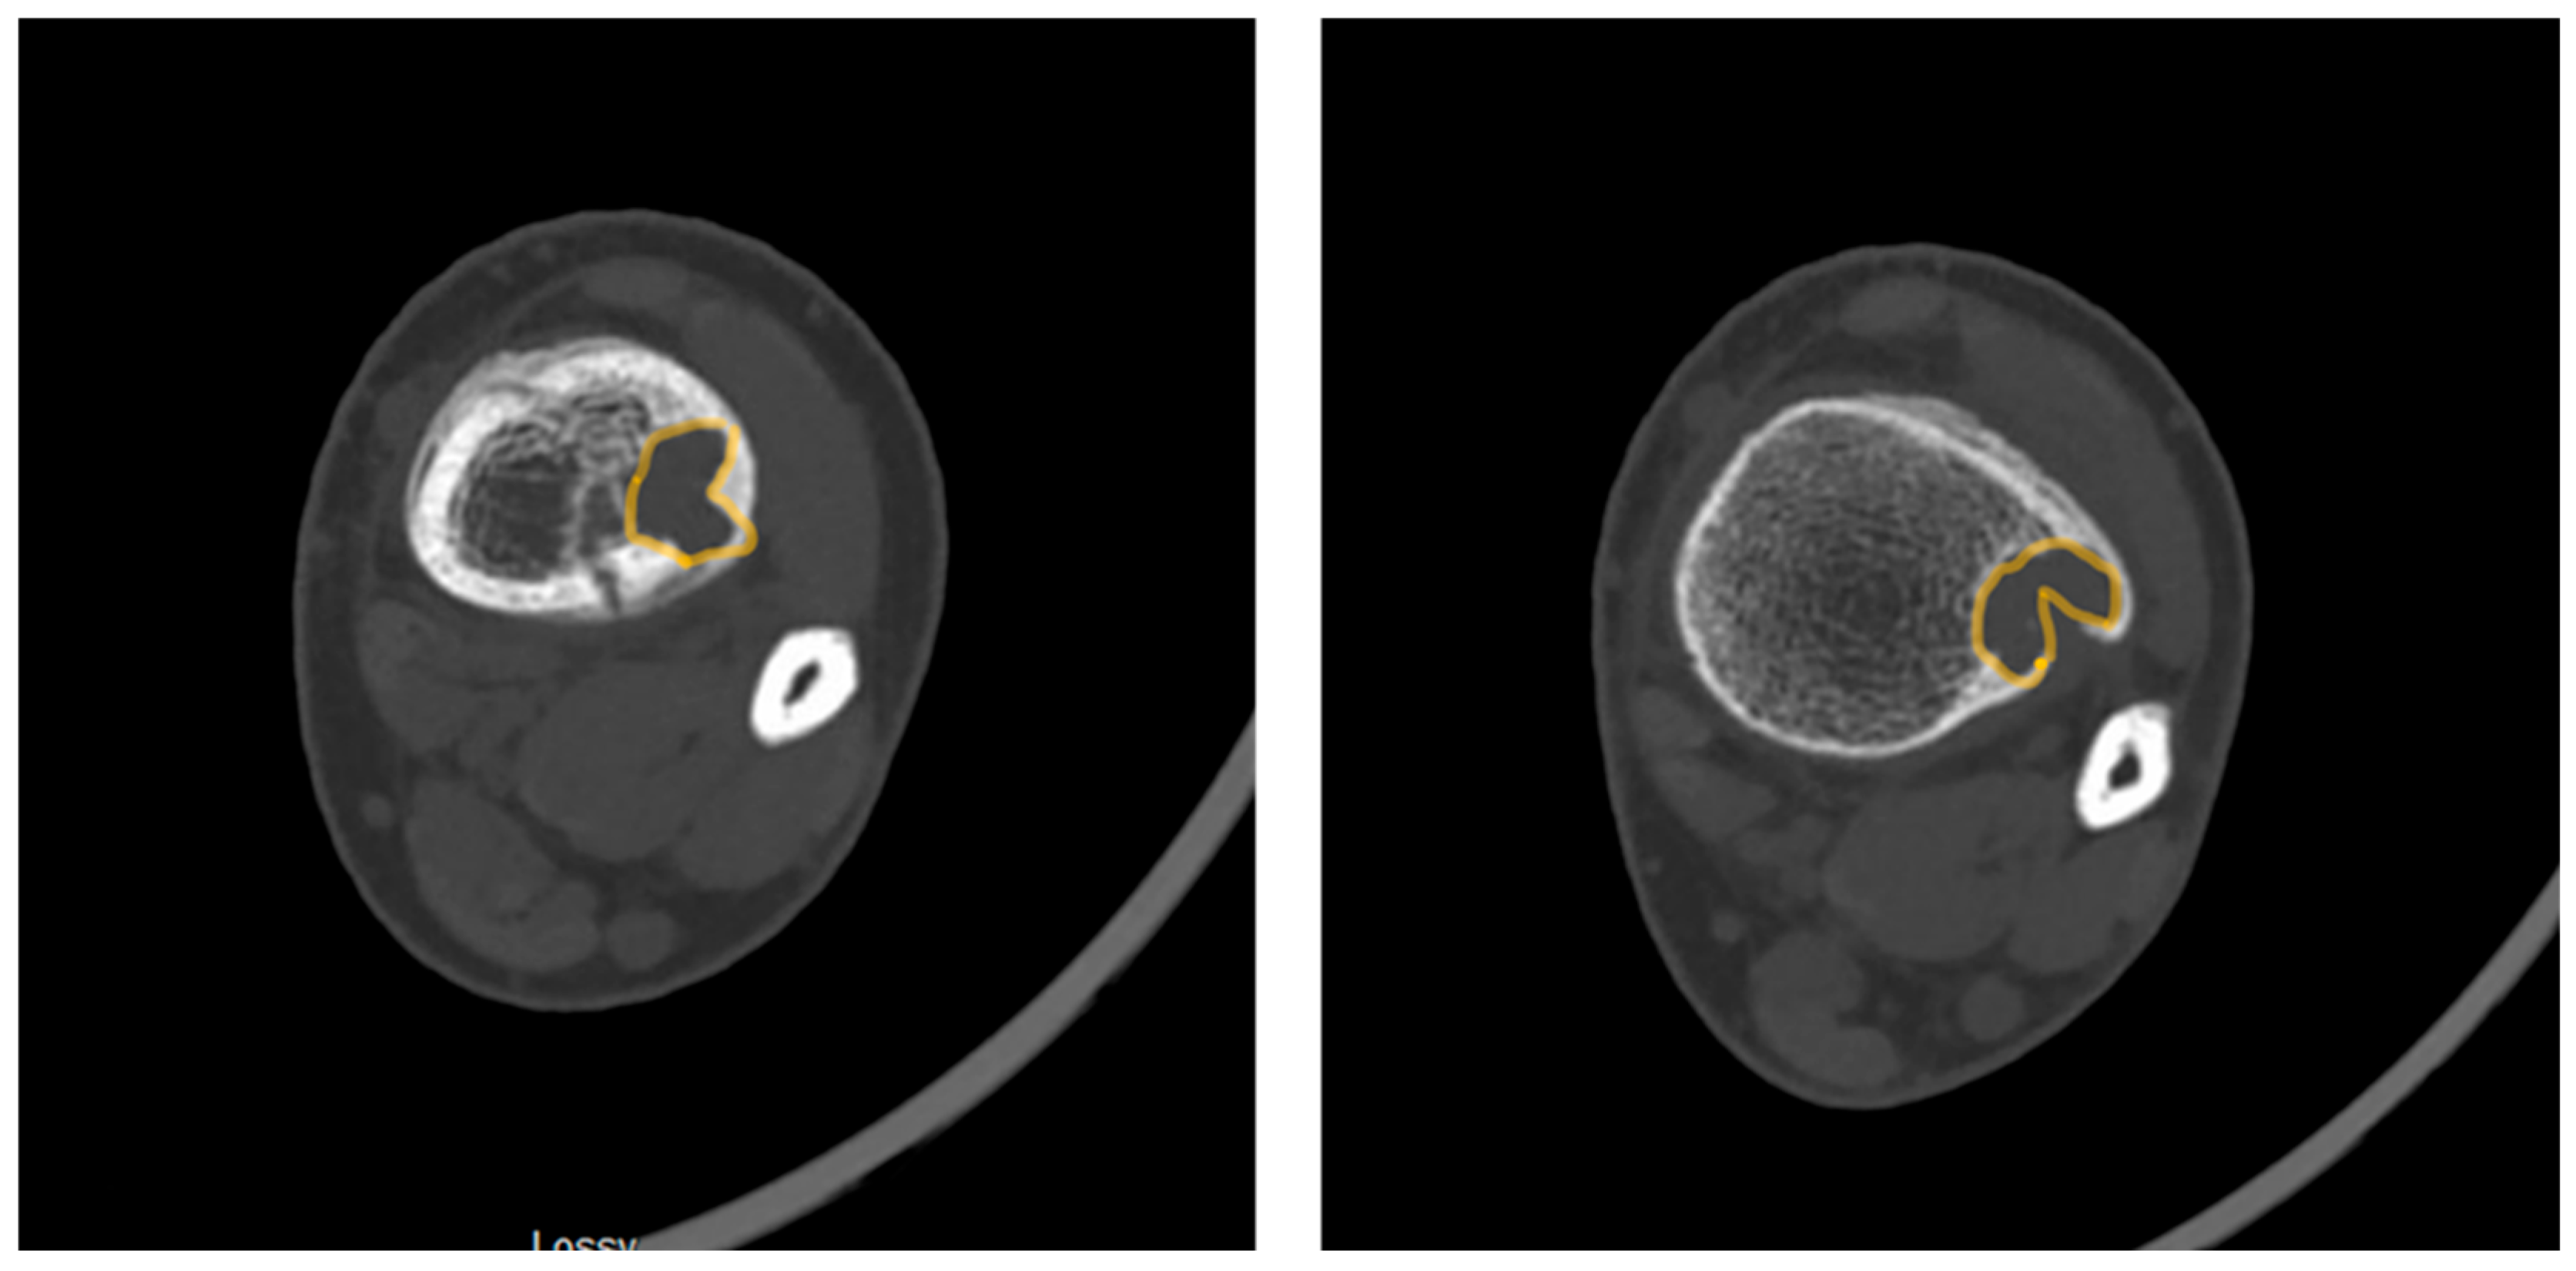

Pac-Man Sign - Proliferation of bone anterior and posterior to the syndesmosis results in a shape which resembles the video game character “Pac-Man”. This sign was found to be highly specific (95%) but not very sensitive (47%) for predicting pathologic fracture. (Figure 3)

• Computed Tomography (CT): CT can be useful for evaluating degree of cortical thinning, which is important when assessing fracture risk [9]. CT is superior for delineating the precise cortical integrity. It allows for quantitative measurement of the cross-sectional area occupied by the lesion, which is a key factor in biomechanical models predicting fracture risk. The signs described above can also be visualized on CT scan. Figure 3 demonstrates a “Pac-Man Sign” on CT of a 13-year-old boy who did have a fracture through an NOF.

Figure 3. Axial computed tomography slices demonstrating the “Pac-Man Sign” in a patient with a pathologic fracture through a distal tibia NOF.